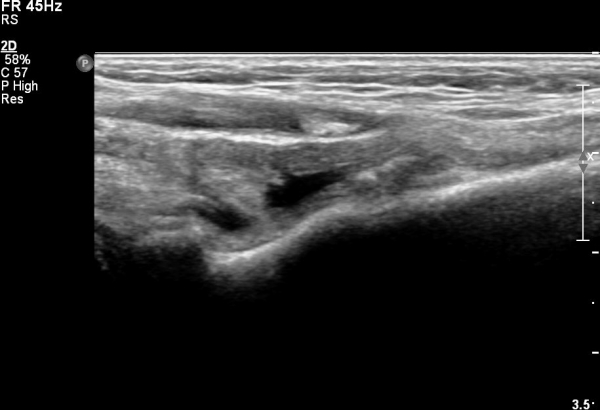

Á¶±Ý´õ ¸»´ÜÀ¸·Î À̵¿ÇÏ´Ï °ÇÀÌ °üÂûµÇÁö ¾ÊÀ½(»çÁø 3).

ÀÌµÎ¹Ú±Ù°Ç Á¾´Ü¸é°Ë»ç¿¡¼­ ¿ä°ñµ¹±âÀÇ µ¹Ãâ°ú °ñ±ØÀÌ °üÂûµÇ°í À̵θ·±Ù°ÇÀº Àú¿¡ÄÚ ºÎÁ¾°ú ¿¬°á ¼Ò½ÇÀÌ °üÂûµÊ(»çÁø 4, 5).